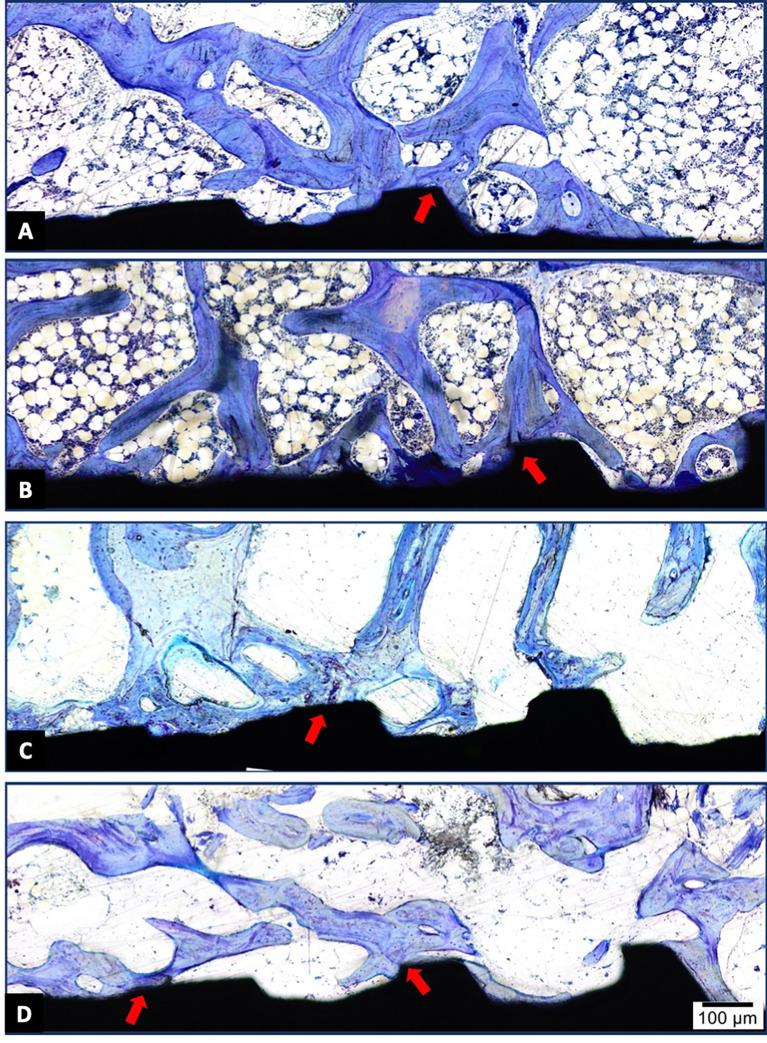

Hydroxyapatite used as a coating for titanium dental implants reduces the time required for osseointegration. Platelet-rich fibrin (L-PRF) releases growth factors and cytokines, enhancing tissue healing and bone regeneration. This study aimed to evaluate histologically, histomorphometrically, and by microcomputed tomography an implant surface coated with nanostructured hydroxyapatite (HAnano), in comparison with a double acid-etched (DAA) surface, both with and without peri-implant grafting with L-PRF, installed in over-instrumented sites in a low-density bone. Five adult sheep (2-4 years old) received twenty 3.5 × 10 mm implants in the iliac crest. Bone-to-implant contact (BIC) and bone-occupied area fraction (BAFo) were evaluated histomorphometrically after an 8-week experimental period. Brown-Forsyth analysis of variance (ANOVA) and Welch's ANOVA test did not identify significant differences between the experimental groups. On average, BIC ranged from 44% (HAnano + L-PRF) to 63% (DAA + L-PRF). µCT analysis revealed that bone volume density in the peri-implant region ranged from 26% (HAnano + L-PRF) to 39% (DAA). No statistically significant differences were observed between the groups. Both implant surfaces studied allowed osseointegration in low bone density sites, independently of peri-implant grafting with L-PRF, after 8 weeks of implantation. While this model provided controlled conditions for evaluating early-stage osseointegration, the absence of functional loading and the relatively short follow-up period should be considered when extrapolating the findings to clinical applications. Future studies should assess these variables under load-bearing conditions with extended observation periods. All the sheep in this study remained alive.